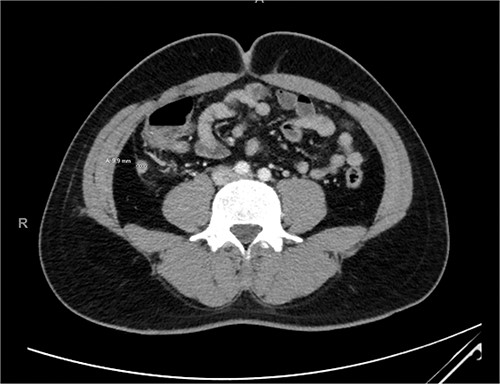

On initial presentation, he had a heart rate of 80 beats per minute, blood pressure of 130/80 mmHg and was apyrexial with a temperature of 37.5°C. On examination, he had localized tenderness over the right iliac fossa without evidence of peritonism. His blood counts revealed a white blood count of 15.0 ×109/l with a neutrophilia of 12.3 × 109/l and a C-reactive protein of 5.3 mg/l. Computed tomography (CT) imaging revealed an acute uncomplicated appendicitis, with the appendix measuring 9.9 mm (Fig. 1).